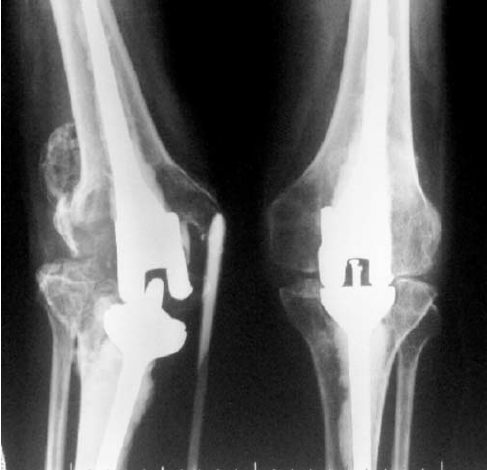

The company ORTHOPEDIC NIKIFOROV was founded in 1998 by the candidate of medical sciences. doctor of orthopedic-traumatologist of the highest category Nikiforov IA Owing to high professionalism and results of work, ORTONIC has gained well-deserved reputation and reputation among colleagues and population of Dnepropetrovsk region and CIS countries (Russia, Moldova, Armenia, etc.). The principle of the enterprise is NO IMPOSSIBLE, it is based on knowledge, experience and active implementation of modern technologies in orthopedics and traumatology. Conservative methods of treatment include individual selection of medicines, therapeutic blockades, manual therapy, massage, physiotherapy (vibration table, magnetotherapy, bioptron, electromyostimulation, etc.), rehabilitation with the suggestion of the necessary concomitant devices and means for the fastest recovery (corsets, bandages, various joint fixators, crutches, walking sticks, etc.). Various minor invasive interventions (chymonucleolysis, vertebroplasty, kyphoplasty, percutaneous nucleoplasty using cold plasma) that are performed on an outpatient basis are successfully used to treat problems associated with spine pathology. The latest modern treatment methods introduced in our company are endoscopic operations using the TYSSES technique of Joimax (Germany) with intervertebral hernias, stenosis and other pathologies of the spine, which allow to avoid complications occurring during open operations and the accompanying general anesthesia. We have many years of successful experience in traditional and modern minimally invasive endoprosthetics of large and small joints, which remains the main direction of our activity. Our company is the exclusive representative of the German company IO International Orthopaedics Holding GmbH, which based on the already known prostheses, its ideas and technological capabilities, has developed and implemented a new concept in hip replacement - an artificial joint prosthesis (ICON). We assist interested colleagues in training the operative technique for installing an artificial joint prosthesis - ICON, both in the workplace and in Germany. For 20 years we have been successfully cooperating with Sanitatshaus Gerd Klinz ortho team, an enterprise that for 20 years has been one of the leading places in Germany for the production of functional prostheses of the upper and lower limbs, as well as cosmetic prostheses of limbs and other body parts (nose, ears, eyeballs, fingers). We have an atmosphere of friendliness and human participation. Politeness, benevolence, the desire to understand and help is the basis of our attitude towards patients. We are always glad to see you and will do our best to make you feel great! We are waiting for you at: Ukraine, Dnepr, Gagarin Ave., 13 (under reconstruction) on all questions to address: tel .: +38 (050) 488-88-92 E-mail: orthonik.ukr@gmail.com Germany, Spine Nano Klinik, Zeppelinstr. 21, Potsdam Tel. +4901801121919 E-mail: kmw.nikiforov@hotmail.de